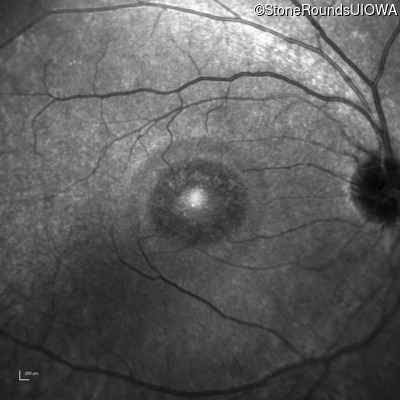

This 44 year old man became photophobic about 6 years ago. He has been taking Imuran since his kidney transplant 23 years ago.

| Senior-Loken Syndrome | NPHP1 | Gly343Arg G(GG)>A(GG) | Deletion of Entire Gene | AR |